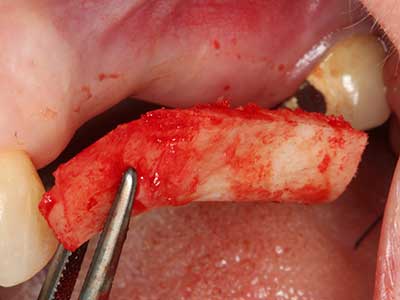

Indication: Bone grafting

Autologous bone transplants are used in the form of blocks, shells, rings and are also combined with bone replacement materials as chips. If the implant site is prepared at the same time as the augmentation, various bone filter systems have proven effective for collecting the resulting bone chips. As an alternative, the implant site can be prepared using a low-speed device without irrigation. If an implant is not inserted, bone chips can be harvested from the periphery with bone scrapers. This is also possible with piezo surgery using specialized attachments that yield higher-quality bone chips compared chips harvested with round drills, as has been confirmed in a study comparing the two methods (Chiriac, Herten et al. 2005).

Piezo surgery has additional advantages when harvesting bone blocks. In addition to the high precision with osteotomy described above, the use of the thin saw tips specifically minimizes loss of material. Greater loss of material during harvesting can be expected with the thicker instrument tips, particularly when using Lindemann drills (Lakshmiganthan, Gokulanathan et al. 2012). The basal separation, which is necessary particularly for retromolar block transplants, is simplified by specially designed rectangular saws, with the result that piezo surgery is viewed as a precise, simple and safe procedure for harvesting retromolar bone blocks (Happe 2007) (Fig. 1-12).